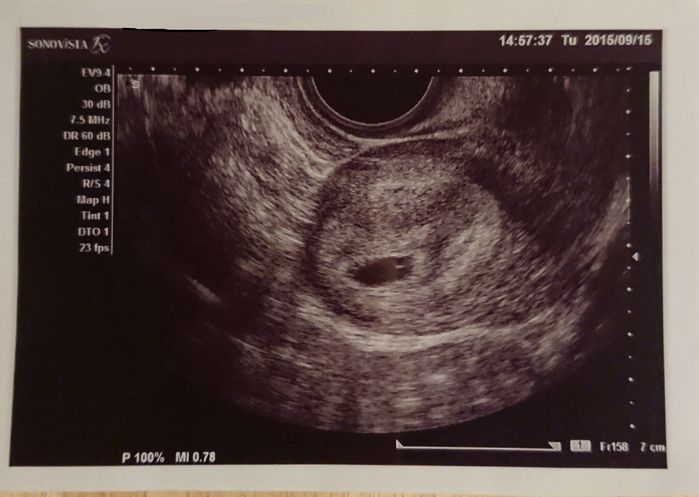

妊娠5週目 胎嚢を確認!

妊娠検査薬で陽性反応が出てから1週間後、産婦人科を受診し、初めてのエコーで胎嚢を確認しました。この時すでにつわりが始まっていたので常にムカムカしている状態です。